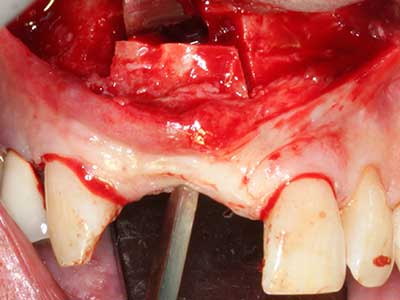

Piezosurgery has additional advantages when harvesting bone blocks. In addition to the high precision with osteotomy described above, the use of the thin saw tips specifically minimizes loss of material. Greater loss of material during harvesting can be expected with the thicker instrument tips, particularly when using Lindemann drills (Lakshmiganthan, Gokulanathan et al. 2012). The basal separation, which is necessary particularly for retromolar block transplants, is simplified by specially designed rectangular saws, with the result that piezosurgery is viewed as a precise, simple and safe procedure for harvesting retromolar bone blocks (Happe 2007) (Fig. 1-12).

Fig. 1: Preparation of a bone cover with the Piezomed (W&H Salzburg, Austria).

Fig. 2: Vertical and horizontal lateral maxillary defect with a high smile line with indication for pre-implant reconstruction.

Fig. 3: Basal separation of the block is easier with specially angled attachments.

Fig. 4: Additional autologous bone chips are harvested with the bone scaler.

Fig. 5: Checking the block size at the recipient site.